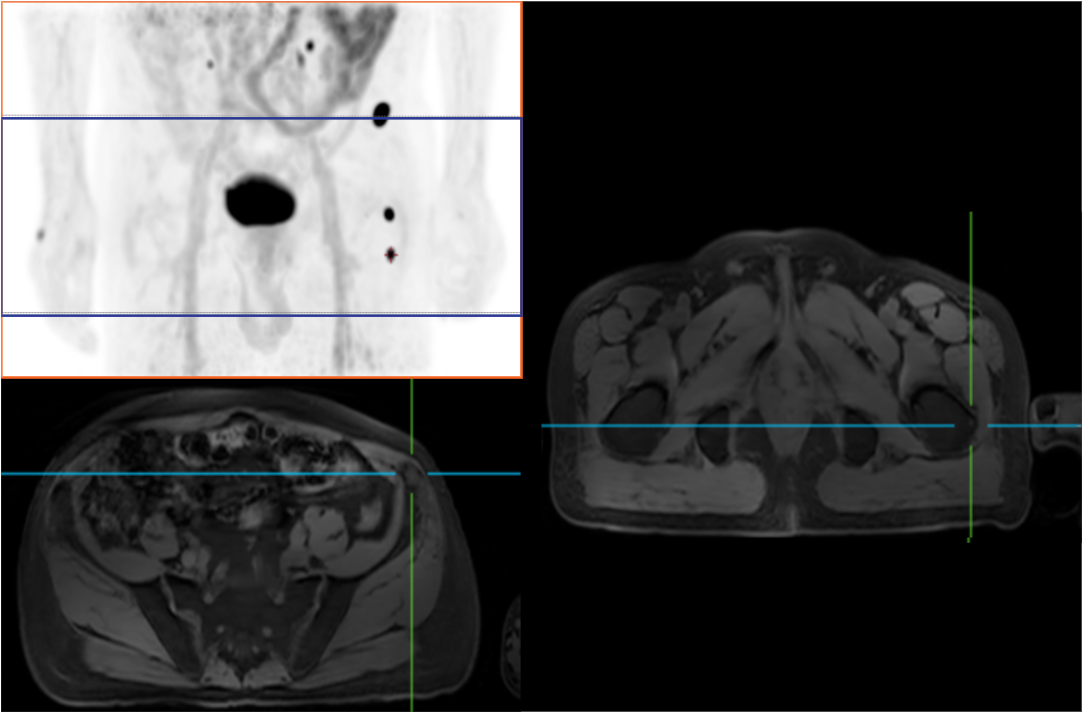

Compared with the conventional PET system with AFOV ranging between 20cm and 25cm, the 32cm long AFOV not only improves the sensitivity of the system, but also basically covers main organs of the whole body and the regional lymphatic system where metastasis may occur, and makes it possible to realize cancer TN staging in one bed position.

Traditionally, a PET/MR scan of a tumor patient takes about 35 to 50 minutes. The long AFOV can further optimize the PET/MR tumor scanning scheme. In other words, it can optimize the decision about whether to scan the whole body based on whether the tumor patient has regional lymphatic metastasis after regional PET/MR scan, potentially saving scan time for patients without metastasis.

In August 2019, Peking Cancer Hospital introduced United Imaging Healthcare's integrated PET/MR to make an in-depth exploration and optimization of cancer TNM staging under long AFOV. More than 500 examples of scanning various organs proved that long AFOV PET/MR could greatly increase the scan range over one bed position and improve the efficiency of cancer TNM staging.

The following are the cases of optimized TNM staging of breast cancer, esophageal cancer, prostate cancer and other diseases under the long axial field of "spatio-temporal integration" ULTRA-clear TOF PET/MR.  Thanks to Capital Medical University Xuanwu Medical Treatment for providing the image.